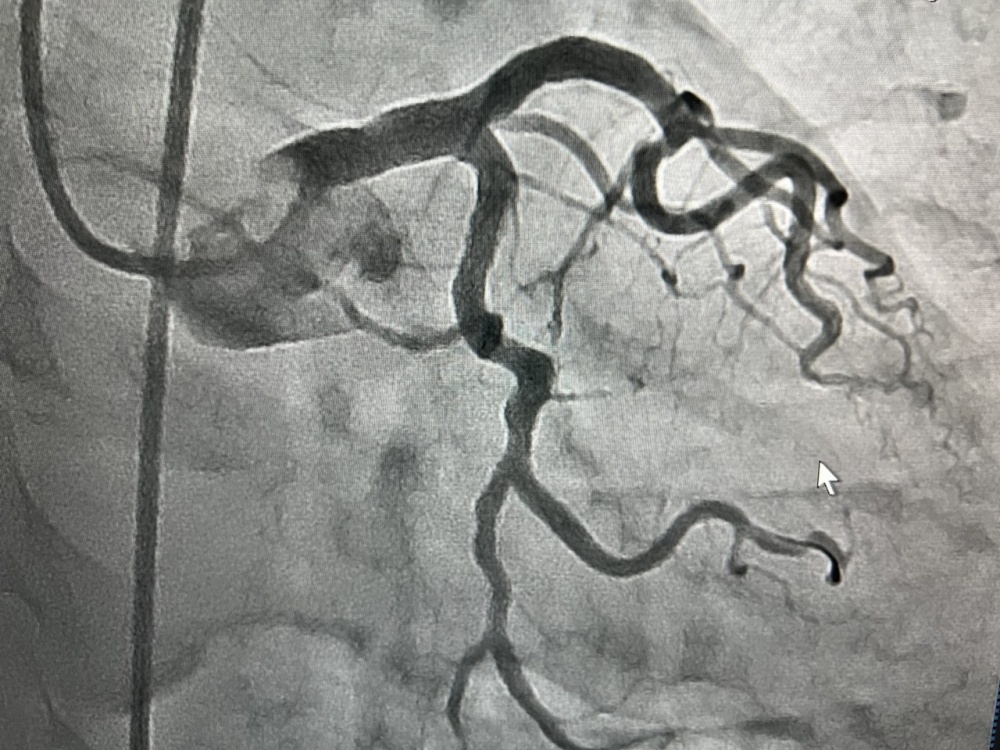

В отделение рентгенохирургии Южного регионального научного центра сердечно-сосудистой хирургии в Жалал-Абаде уже с марта привозят больных с различными сердечными патологиями, в том числе с острым коронарным синдромом из сел и райцентров Жалал-Абадской области. В начале апреля 28 пациентам проведена ангиография, благодаря этому методу контрастного рентгенологического исследования врачи на экране видят чёткое изображение сосудов сердца, их сужения и аномалии. Нескольким из этих больных рентгенохирурги установили стенты, чтобы предотвратить инфаркт миокарда, четверым - уже с острым инфарктом миокарда. Оказана необходимая помощь и пациентам при других формах коронарных синдромов.

На снимках представлено видео стеноза аортального клапана до лечения, в процессе баллонной дилатации и после имплантации и стентирования